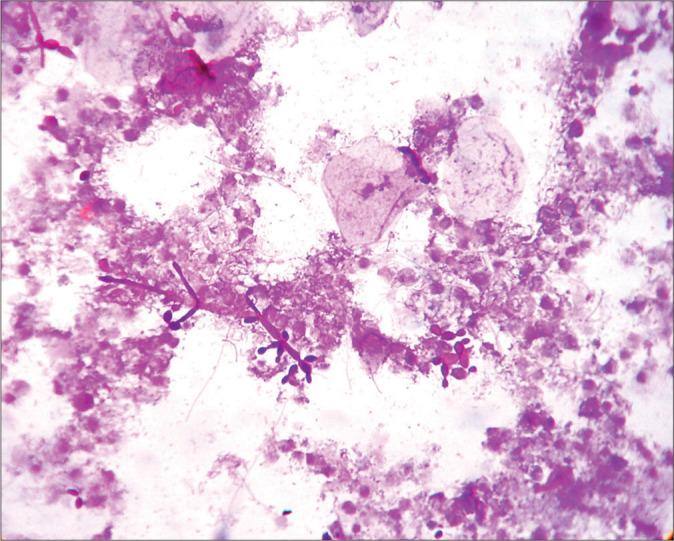

Fluids are one the most common specimens received in cytology laboratories. The presence of erythrocytes may obscure the cells in the smears, making the diagnosis, and identification of cells difficult. Many techniques are being used by laboratories to eliminate these erythrocytes. The present study was undertaken to improve the quality of cytology smears of hemorrhagic samples by comparing three different techniques, namely, Carnoy's fixative (CF), modified CF, and normal saline rehydration technique (NSRT) to hemolysis red blood cells (RBC) present in the smear background for better cytological assessment. The present study was a prospective study done over 1 year 6 months from November 2012 to March 2014, in the Department of Pathology in a Tertiary Care Rural Medical College.

MATERIALS AND METHODS

All hemorrhagic effusions received in the department of pathology were processed using CF, modified CF, and NSRT. The background of the smear and cytomorphological details with two different stains was analyzed. The Chi-square test was used to find out the association of different techniques in the reduction of RBC.

RESULTS

More than 60% reduction of RBCs in the smear was noted in 85.40%, 14.60%, and 15.60% by NSRT, modified CF, and CF, respectively. Staining was better and nuclear features were best preserved in NSRT.

CONCLUSION

NSRT is the best, simple, and cheaper technique to lyse RBC in the hemorrhagic fluid. It also shows better staining and well-preserved cytomorphological features of the cell.